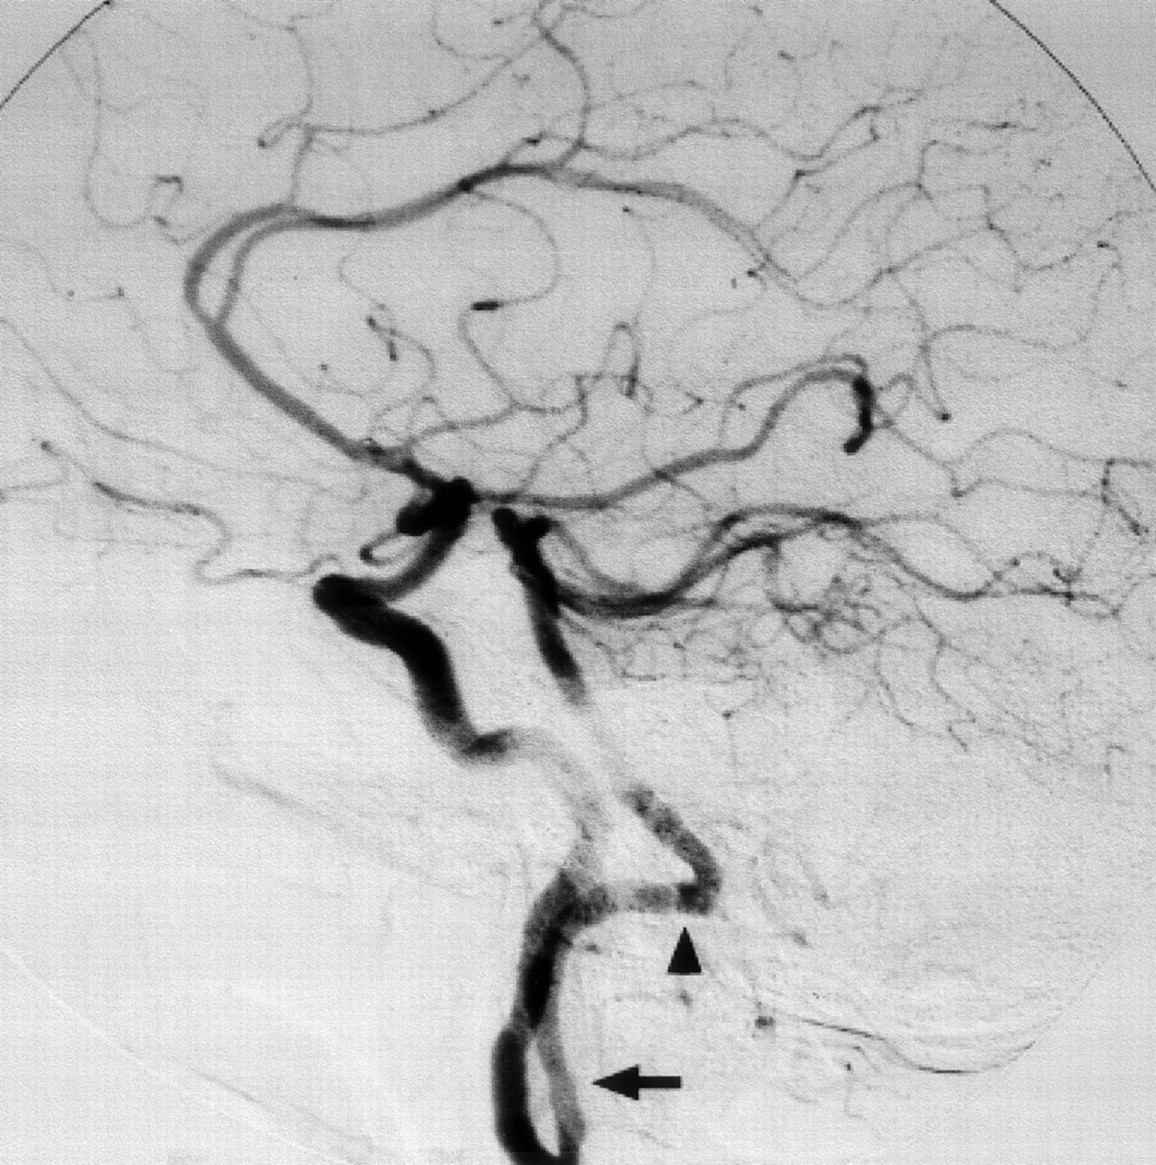

Right common carotid artery digital subtraction arteriogram, lateral projection. Proatlantal artery (arrow) originates from the internal carotid artery. The vessel extends to the posterior aspect of atlas with a horizontal sweep characteristic of a type 1 proatlantal artery (arrowhead) before turning upward to join the horizontal segment of the vertebral artery.

The horizontal portion of vertebral arteries were constituted by two vessels originating from the internal carotid arteries bilaterally (Fig 1). Selective catheterization of both common carotid arteries confirmed the findings of the MRA. An aortic arch arteriogram revealed absence of the vertebral arteries bilaterally (Fig 2). Evaluation of right carotid system demonstrated the origin of anastomostic vessel from the internal carotid artery at the level of the C2 vertebra. The vessel coursed superiorly until the atlantooccipital junction and continued dorsally before entering the skull through foramen magnum (Fig 3). Evaluation of the left carotid system showed a smaller vessel originating from the internal carotid artery at the level of C2 vertebra. This vessel also coursed superiorly and entered skull through foramen magnum after proceeding dorsally (Fig 4). The basilar artery and both posterior cerebral arteries were supplied by these vessels, especially by the dominant right one. Atherosclerotic plaques were present at the proximal portion of both internal carotid arteries and right persistent proatlantal artery. They probably were the source of the emboli causing the neurologic symptoms we have described.